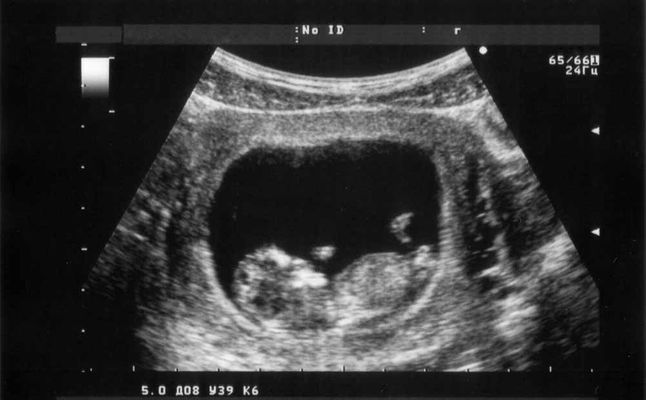

مراحل نمو الجنين بالصور السونار

مراحل نمو الجنين بالصور السونار لدينا خطوات مراحل نمو الجنين في فتره الحمل بالسونار صور حزينه

مراحل الحمل بالصور السونار بمبي

مراحل تطور الجنين بالسونار مفهرس

صورة التراساوند للجنين في الاسبوع الثامن موسوعة

شكل الجنين بالسونار في الاسبوع السادس عشر

شكل الجنين في الاسبوع الثالث عشر بالسونار صور وفيديو مجلة أبدعي

صورة التراساوند للجنين في الاسبوع الثامن موسوعة